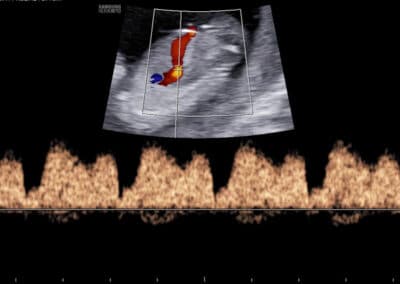

Dopplerovské vyšetření ductus venosus – normální nález (pozitivní a-vlna s PI do 1.3)

Dopplerovské vyšetření ductus venosus – abnormální nález (reverzní a-vlna s PI nad 1.3)

UZ vyšetření průtoku v ductus venosus dle FMF protokolu

Protokol pro správné Dopplerovské vyšetření průtoku krve v ductus venosus:

CRL 45-84 mm (11-13+6 týden) Vyšetření musí být provedeno během klidové fáze (absence pohybů) plodu Zvětšení (hrudník a břicho plodu vyplňují většinu obrazovky) Mid-sagitální řez tělem plodu, barevné Dopplerovské zobrazení toku krve v pupečníkové žíle, ductus venosus a v srdci Gate 0.5-1mm přes ductus venosus (místo aliasingu – světlé barvy při Dopplerovském vyšetření) Odklon průběhu v ductus venosus 0-30º od vertikální osy Nízký filtr (50-70 Hz) Vysoká rychlost posunu křivky (2-3cm/s)